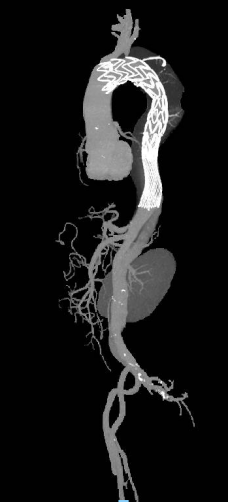

3. 主动脉全程CTA,头部血管+颈部血管CT增强报告(2024-10-28)

报告提示① 主动脉夹层(B型);② 右侧迷走锁骨下动脉;③ 右侧椎动脉纤细;④ 双侧胸腔积液,双肺膨胀不全;⑤ 头、颈部血管粥样硬化,部分管腔轻度狭窄;⑥ 考虑右侧小脑半球、右侧额叶脑梗死可能,请结合临床,必要时进一步检查(图2、图3)。

图2 2024-10-28患者主动脉全程CTA,头部血管+颈部血管CT增强报告

图3 2024-10-28患者主动脉全程CTA图像